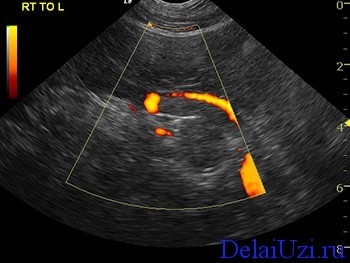

Дуплексное сканирование позволит оценить крупные сосуды находящиеся рядом с исследуемым органом. Особенность этого типа исследования показывает качество кровотока в нижней полой вене, в верхних брыжеечных вене и артерии, в чревном стволе и селезеночной вене. Расшифровка показаний при дуплексном сканировании говорит о том, страдает ли орган от недостаточного тока крови и есть ли препятствия на пути потока в виде опухолей. Если такие изменения имеются, нужно замерить их размеры и структуру ткани.

Особую важность представляет состояние протока железы (Вирсунгов проток). Если есть какие-либо изменения, то возникают подозрения на опухоль головки железы или панкреатит.

Первый этап заболевания характеризуется увеличением размеров железы. Контуры становятся нечеткими, а панкреатический проток значительно расширяется. Часто патологические изменения затрагивают и соседние органы, что также приводит к повышению их эхогенности. Увеличенная поджелудочная железа может сжимать крупные сосуды, нарушая кровоснабжение близлежащих органов. Эти изменения хорошо видны при дуплексном сканировании, даже если пациент не подготовился должным образом.